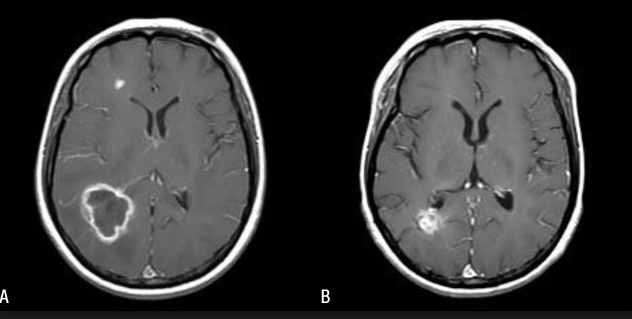

scarecrow with spots at kidney, heart, head black spot with ring: Renal failure

Endocarditis

Ring-enhancing brain lesion (seizures, focal neuro deficits, with symptoms)

soap bubbles on head: Causes "soap bubble" lesions in gray matter